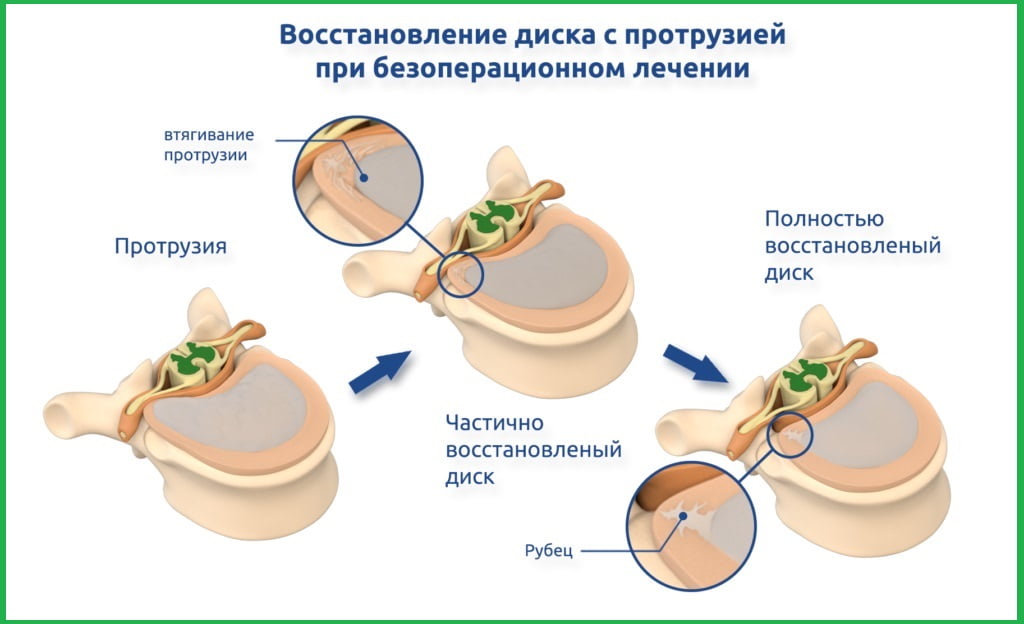

Раздел: Необычные решения